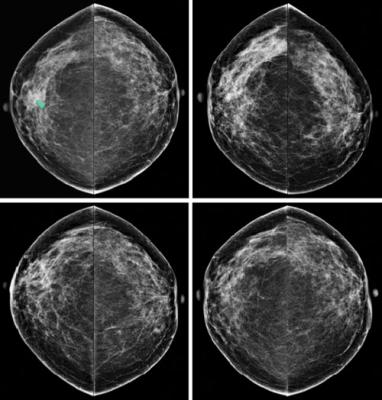

October 31, 2017 — Some women, because of genetic predisposition, personal or family history, have a higher than average lifetime risk of developing breast cancer. For those women, earlier magnetic resonance imaging (MRI) is recommended for cancer screening.

For the study, investigators from Madigan Army Medical Center analyzed data on 1,057 women who had a 20 percent or greater lifetime risk of developing breast cancer. The screenings were offered based on their high-risk status, and not because of mammography results. Between 2015 and 2016, these women were offered MRI screenings. The aim of this analysis was to assess whether these higher risk women actually got the imaging test. Overall, the study showed that only 23 percent (247 women) underwent MRI screening.